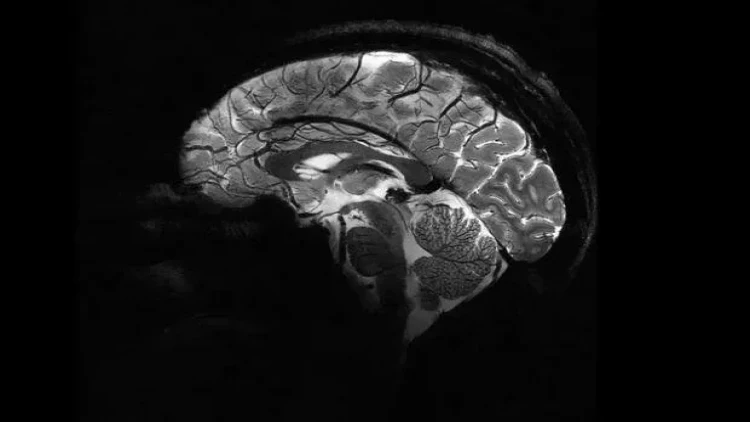

Elm adamları insan beyninin ən aydın görüntüsünü dərc ediblər. Şəkli dünyanın ən güclü maqnit rezonans tomoqrafiya (MRT) cihazı ilə əldə etmək mümkün olub.

meqale.com oxuya istinadən bildirir ki, fotonu Fransa Atom Enerjisi və Alternativ Enerji Agentliyi (CEA) yayımlayıb.

Bildirilib ki, "Iseult" adlı MRT cihazı ilə çəkilən şəkil 20 ildən çox davam edən araşdırma nəticəsində əldə olunub.

Araşdırmalar çərçivəsində MRT cihazının son bir neçə ayda təxminən 20 sağlam könüllü üzərində sınaqdan keçirildiyi və ən aydın beyin görüntüsünün təxminən dörd dəqiqə ərzində əldə edildiyi ifadə edilib.

Açıqlamada qeyd olunub ki, 11,7 Tesla maqnit gücünə malik "Iseult" cihazı ilə qısa müddətdə çəkilən görüntüləri xəstəxanalarda istifadə edilən cihazlarla əldə etmək saatlar çəkə bilər.